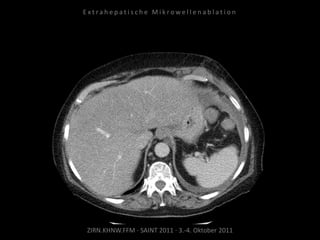

Verlaufskontrolle:

CT 24.06.2010

Behandelte Metastase nicht progredient.

Neu ist ein subkapsuläres Biliom DD

Serom DD Hämatom der Leber.